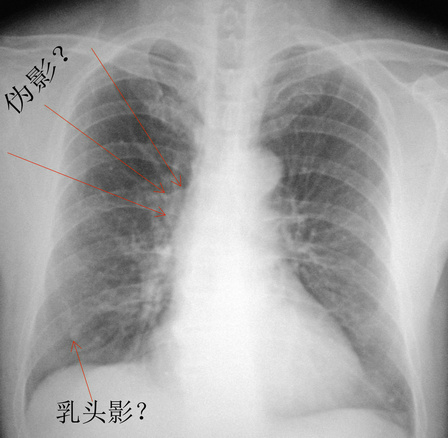

男.66.慢支炎数年.请会诊

右下肺结节是否乳头影透视一转一目了然,至于右肺门区软组织影,可结合ct检查,既然觉得不正常就不要放过,没事大家都放心,别留遗憾。

符合慢性支气管炎表现。

两肺纹增多增粗,支持慢支。